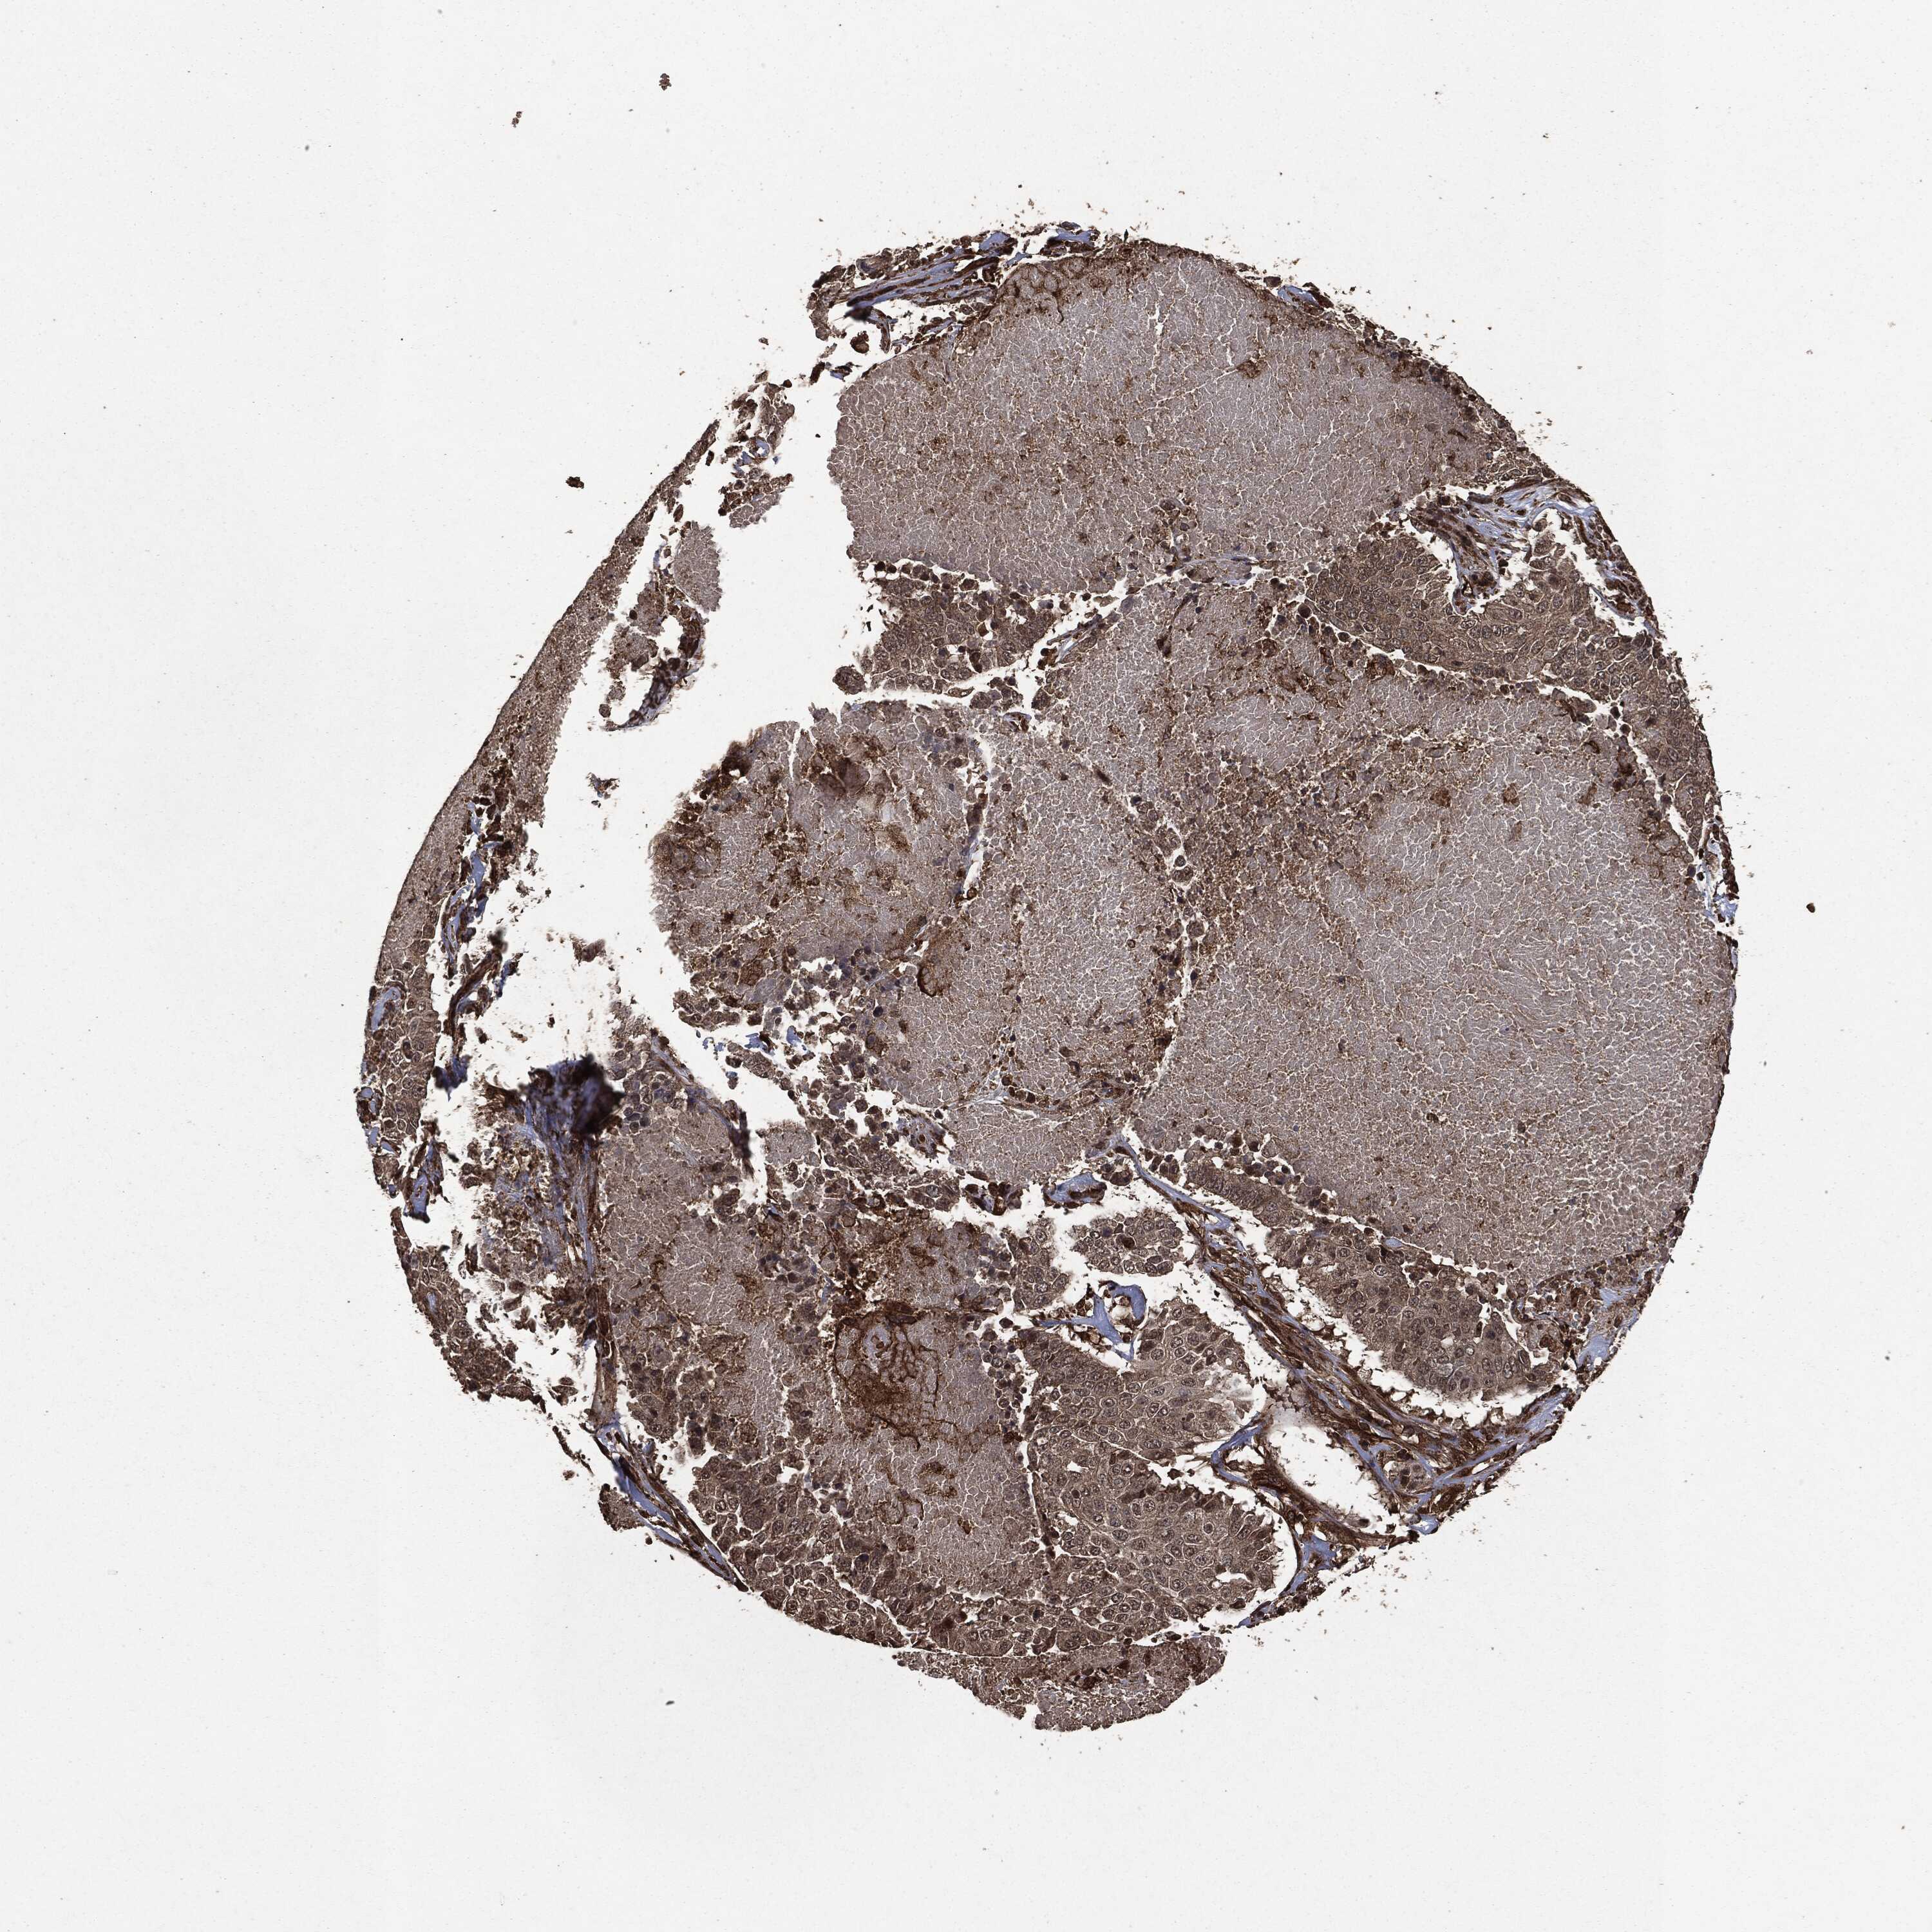

LUNG SQUAMOUS CELL CARCINOMA (TCGA) - Interactive survival scatter ploti

The Survival Scatter plot shows the clinical status (i.e. dead or alive) for all individuals in the patient cohort, based on the same data that underlies the corresponding Kaplan-Meier plots. Patients that are alive at last time for follow-up are shown in blue and patients who have died during the study are shown in red.

The x-axis shows the expression levels (FPKM) of the investigated gene in the tumor tissue at the time of diagnosis. The y-axis shows the follow-up time after diagnosis (years). Both axes are complimented with kernel density curves demonstrating the data density over the axes. The top density plot shows the expression levels (FPKM) distribution among dead (red) and alive patients (blue). The right density plot shows the data density of the survived years of dead patients with high and low expression levels respectively, stratified using the cutoff indicated by the vertical dashed line through the Survival Scatter plot. This cutoff is automatically defined based on the FPKM cutoff that minimizes the p-score. The cutoff can be changed by dragging the vertical line or by entering a cutoff value in the square labeled "Current cut-off".

Under the Survival Scatter plot the p-score landscape (black curve; left axis) is shown together with dead median separation (red curve; right axis). Dead median separation is the difference in median mRNA expression between patients who have died with high and low expression, respectively. It is calculated as follows: median FPKM expression of dead patients with high expression - median FPKM expression of dead patients with low expression. This is intended to aid the user in visually exploring custom cutoffs and the associated p-scores and dead median separation.

Individual patient data is displayed and can be filtered by clicking on one or more of the category buttons on the top of the page. Categories describing expression level and patient information include: high, low, alive, dead, female, male and tumor stages. The scale of the x-axis can be toggled between linear and log-scale by clicking on the "x log" button. Mouse-over function shows TCGA ID, patient information and mRNA expression (FPKM) for each patient.

& Survival analysisi

Kaplan-Meier plots summarize results from analysis of correlation between mRNA expression level and patient survival. Patients were divided based on level of expression into one of the two groups "low" (under cut off) or "high" (over cut off). X-axis shows time for survival (years) and y-axis shows the probability of survival, where 1.0 corresponds to 100 percent.

HRAS is not prognostic in Lung Squamous Cell Carcinoma (TCGA)

: 37.27

P scorei

N/A

Average pTPM 32.7

Number of samples 489